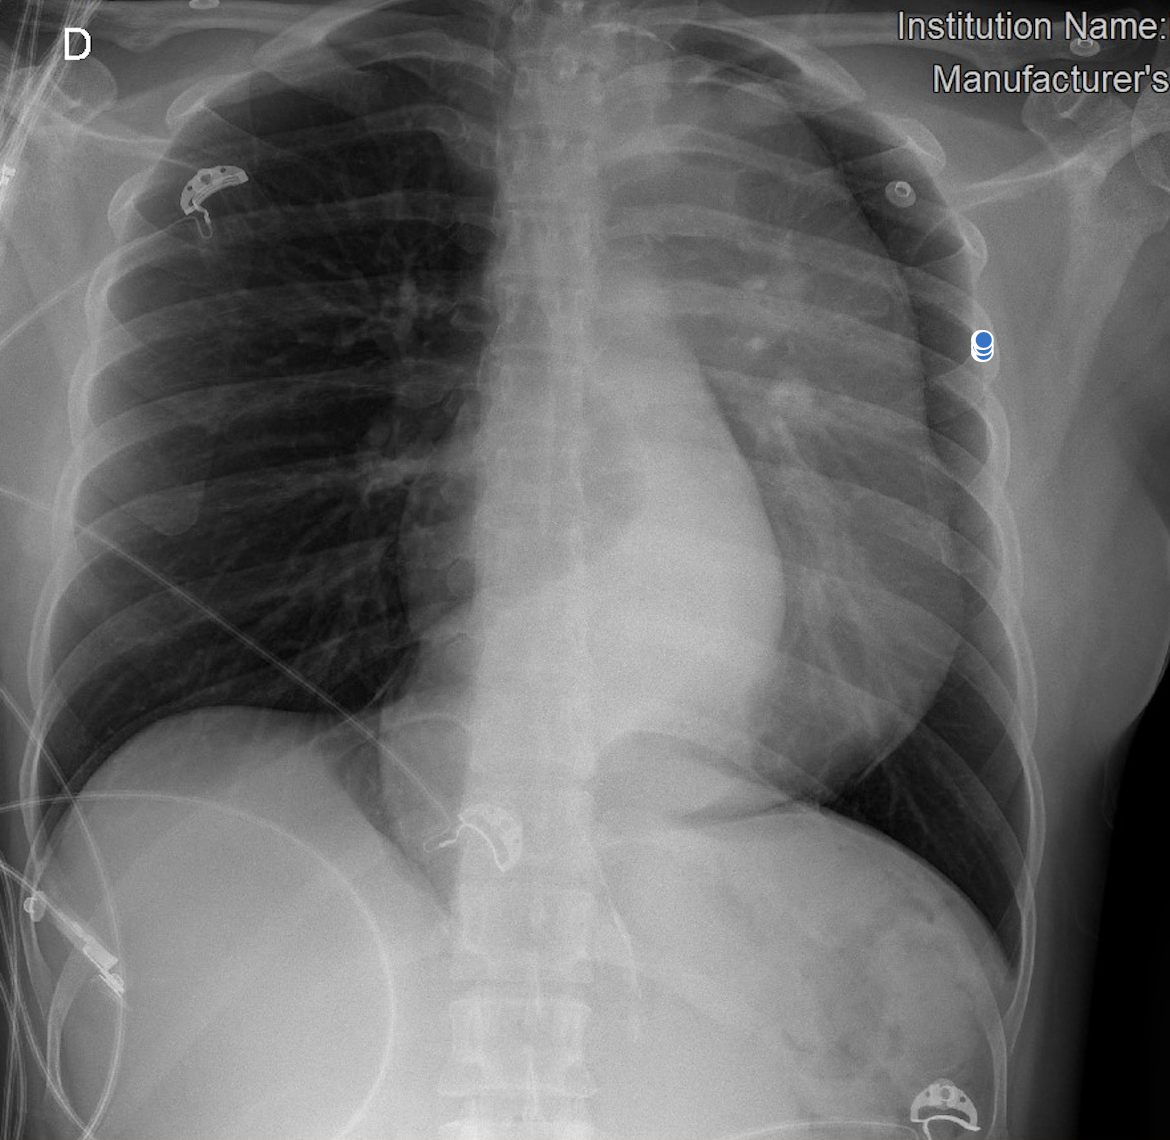

Initial workup

Chest X-ray showed mediastinal widening. CT angiography revealed a fusiform thoracoabdominal aortic aneurysm (89 × 85 mm, 221 mm length) from T6 to L2, with a dissection flap from the coeliac trunk to the infrarenal segment (Stanford B, DeBakey III), plus intramural thrombus and mural calcifications. A 10 mm flap in the proximal coeliac trunk and an intimal tear at the origin of the left subclavian artery (extending 54 mm) were also seen. Additional findings: left pleural effusion and hepatic haemangiomas.